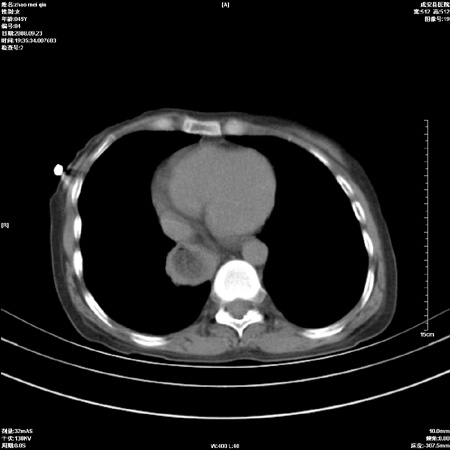

标题: CT15861:女 60 外伤后1小时 胸疼 [打印本页]

标题: CT15861:女 60 外伤后1小时 胸疼

外伤后1小时 胸疼 是外伤后引起的吗?

食道扩张明显下端逐渐变窄,倒像贲门失迟缓

食道扩张明显下端逐渐变窄,大量食物存留,象贲门失迟缓症。

非外伤性改变,典型的贲门失迟缓症